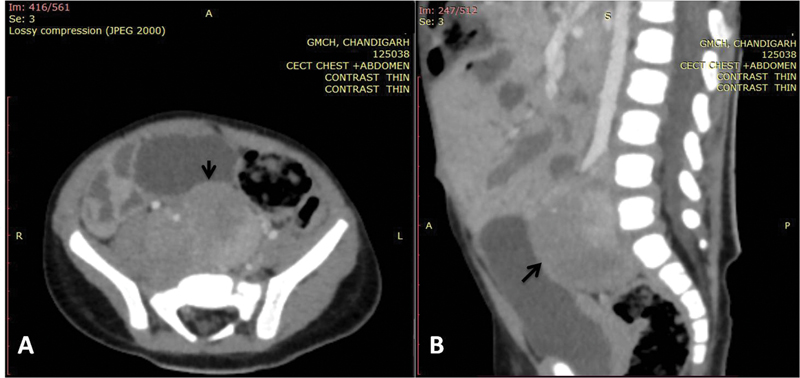

<video width="320" height="240" controls="">In view of the clinical picture, the possibility of opsoclonus-myoclonus-ataxia syndrome (OMAS) was considered. The electroencephalography revealed no evidence of seizure activity. Magnetic resonance imaging of brain was grossly normal. Chest X-ray and ultrasound abdomen showed no mass. Cerebrospinal fluid analysis revealed acellular fluid with sugar and protein of 70 and 20 mg/dL, respectively. Contrast-enhanced computed tomography (CECT) of abdomen revealed a large heterogeneously enhancing lesion measuring 2.5 × 3.1 × 4.5 cm in the retroperitoneum involving organ of Zuckerkandl ([Fig. 1A and B]). This was followed by a fluorine 18 fluorodeoxyglucose single-photon emission computerized tomography that showed increased tracer uptake (maximum standardized uptake value: 6.9, 4.6 × 2.6 × 4.8 cm) in the retroperitoneal soft tissue mass implicating somatostatin receptor expressing retroperitoneal soft tissue mass. Due to financial constraints, urine catecholamine metabolites were not assessed.

| Fig 1 :(A) Axial and (B) sagittal image of contrast-enhanced computed tomogram of abdomen showing well-defined heterogeneously enhancing mass lesion (black arrows) in the retroperitoneum, in the midline and on the right side, extending cranially from the level of aortic bifurcation and caudally into the rectovesical pouch in the pelvis till S2-S3 vertebral level displacing the right iliac vessels anterolaterally.

| Fig 1 :(A) Axial and (B) sagittal image of contrast-enhanced computed tomogram of abdomen showing well-defined heterogeneously enhancing mass lesion (black arrows) in the retroperitoneum, in the midline and on the right side, extending cranially from the level of aortic bifurcation and caudally into the rectovesical pouch in the pelvis till S2-S3 vertebral level displacing the right iliac vessels anterolaterally.